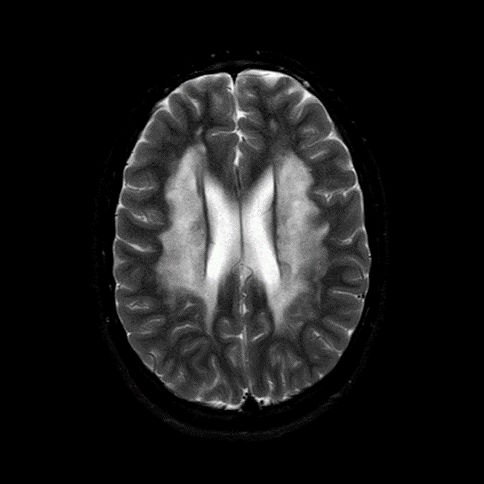

- A) Aksiyel T2A ve koronal T2A sekanslarda sentrum semiovale, korona radiata ve bazal ganglionlar düzeyinde bilateral frontoparietal derin periventriküler beyaz cevherde birleşme eğilimi gösteren hiperintens gliotik sinyal değişiklikleri (oklar) ve aksiyel T2A serilerde servikal spinal kordda posterior kolonda, lateral kesimlerde sinyal artımları (oklar) izlendi.

- LBSL, karakteristik radyolojik özelliklere sahiptir. MRG’de tipik olarak bilateral ve simetrik beyaz cevher sinyal değişiklikleri görülürken, subkortikal U lifleri, internal kapsülün posterior kolları, trigeminal sinir traktları, serebellum, korpus kallozumun spleniumu, medulla oblongata ve omurilikteki dorsal kolonlar ile lateral kortikospinal traktlar genellikle korunur.

- Etkilenen bölgelerde T1’de hipointens, T2/FLAIR’da hiperintens sinyal değişiklikleri izlenir. DWI’de lezyonların periferinde kısıtlı difüzyon görülebilir. MRS’de beyaz cevherde laktat artışı saptanabilir, ancak bu her hastada mevcut değildir.

- LBSL tanısında majör kriterler; subkortikal U lifleri korunmuş serebral beyaz cevher, servikal düzey dahil omurilik dorsal kolonları ve lateral kortikospinal traktlar, medulla oblongata piramitleri veya medial lemniskus dekusasyonu tutulumu iken; minör kriterler korpus kallozum spleniumu, internal kapsül posterior kolu, superior ve inferior serebellar pedinküller, trigeminal sinir traktları, mezensefalik trigeminal yollar, medulla oblongata anterior spinosebellar traktları ve serebellar beyaz cevherdeki sinyal değişiklikleridir.